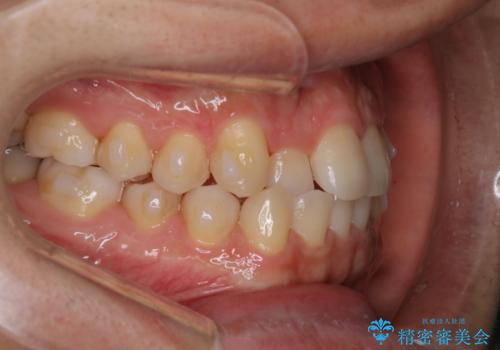

- 前歯のがたつきを主訴に来院されました。初診時、右上2番の口蓋側転位と右下7番の舌側傾斜が認められました。

インビザラインにてIPRと歯列弓拡大を行い、ゴム掛けで噛み合わせを改善する治療計画を立てました。

治療期間1年で、主訴である前歯のがたつきを改善出来、

奥歯の噛み合わせも良くなりました。